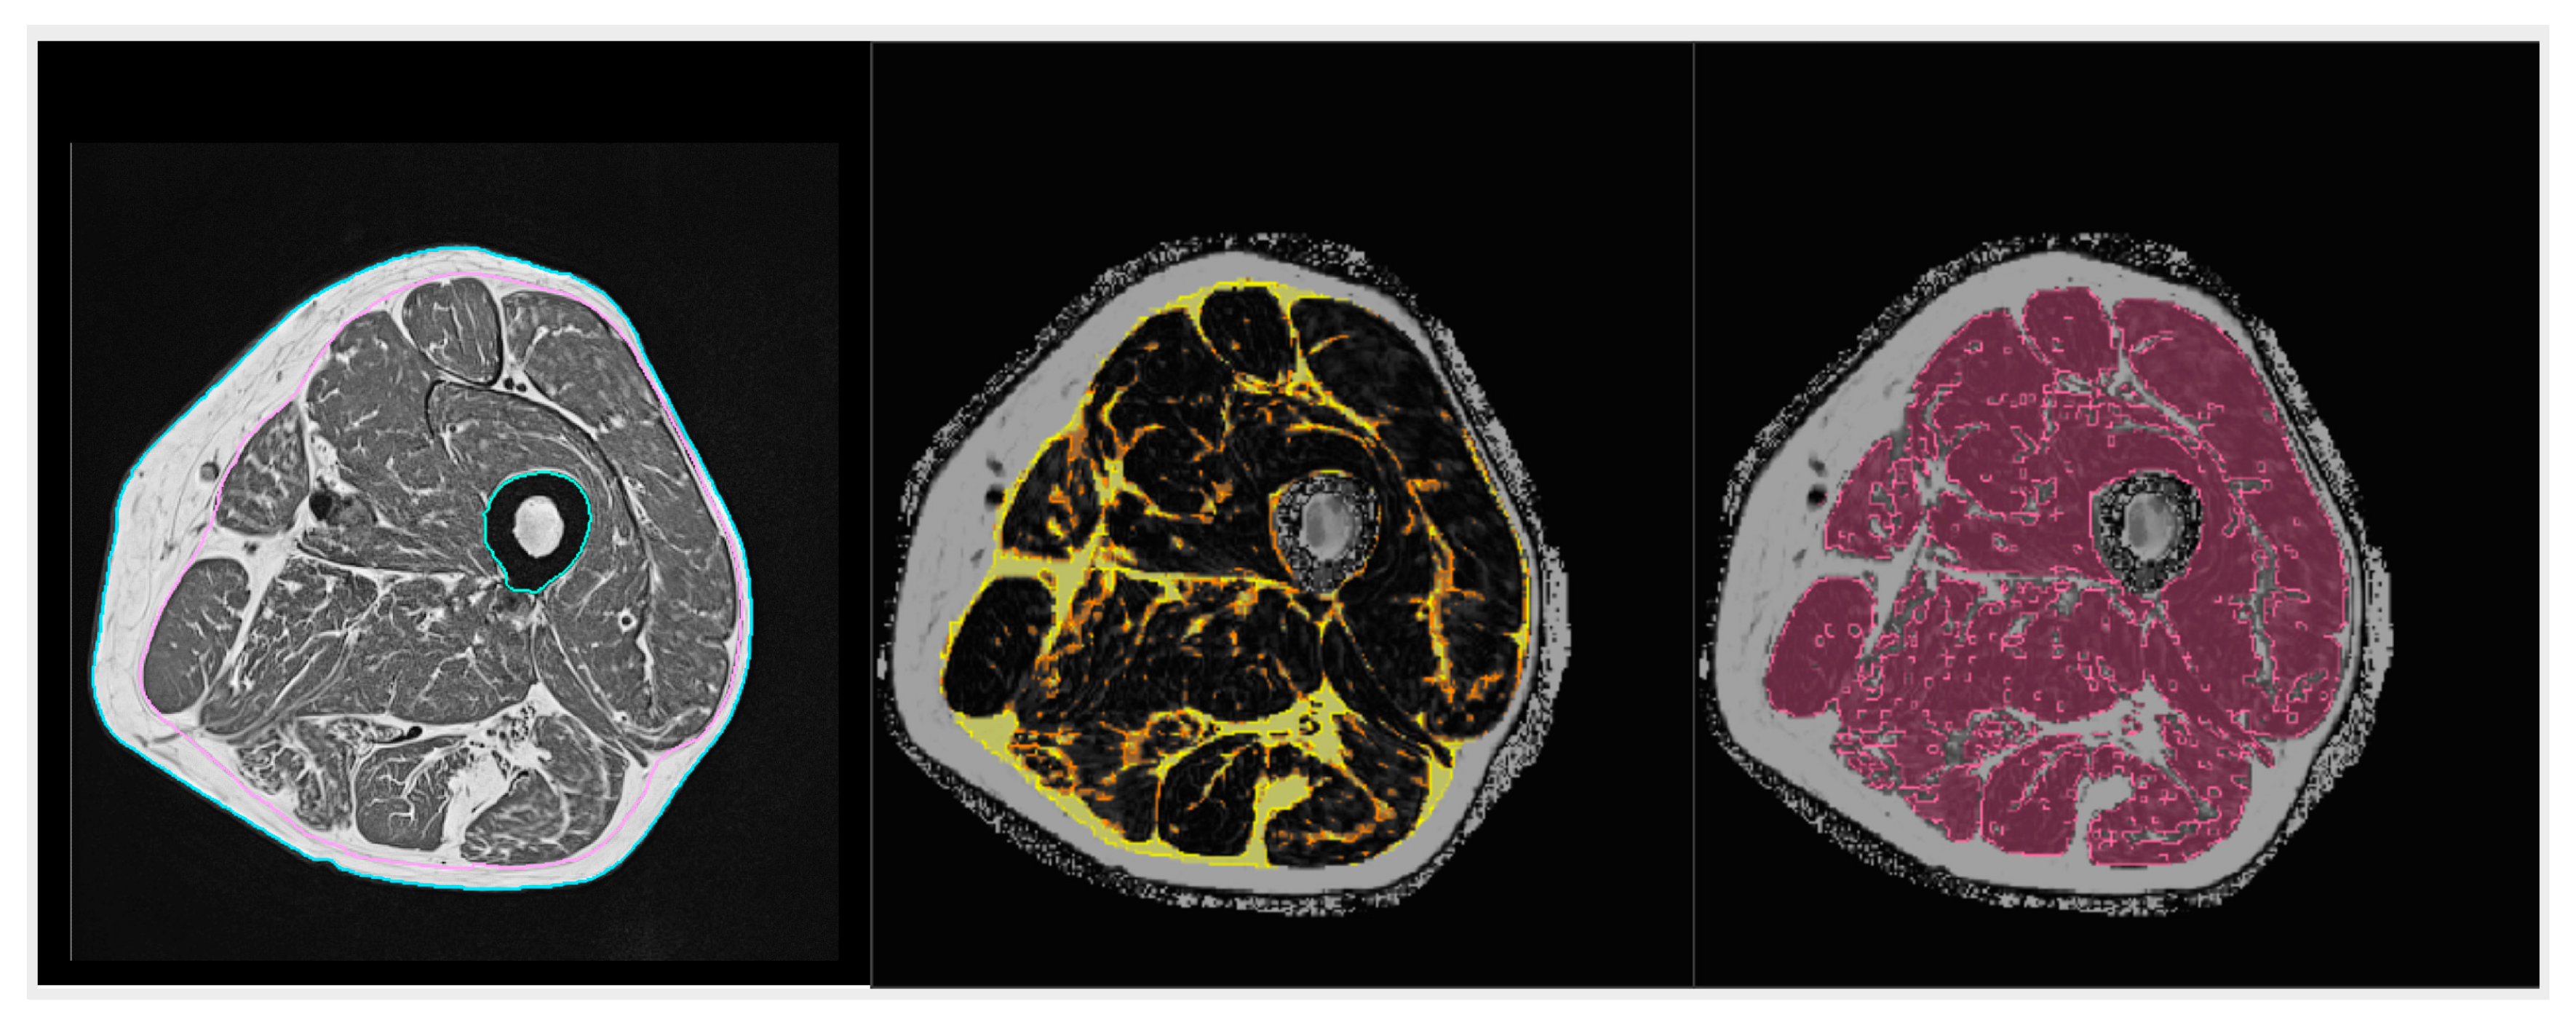

- Grimm, A.; Meyer, H.; Nickel, M.D.; Nittka, M.; Raithel, E.; Chaudry, O.; Friedberger, A.; Uder, M.; Kemmler, W.; Engelke, K.; et al. Repeatability of Dixon magnetic resonance imaging and magnetic resonance spectroscopy for quantitative muscle fat assessments in the thigh. J. Cachex- Sarcopenia Muscle 2018, 9, 1093–1100. [Google Scholar] [CrossRef] [PubMed]

| MRI T1 | thigh abdomen paraspinal muscle | SAT, VAT area/volume (cm2/cm3) IMAT area/volume (cm2/cm3) muscle area/volume (cm2/cm3) |

| MRI Dixon | whole body thigh paraspinal muscle | FF (%) WF (%) |

| CT | thigh abdomen paraspinal muscle | SAT, VAT area/volume (cm2/cm3) IMAT area/volume (cm2/cm3) muscle area/volume (cm2/cm3) muscle density (HU) |